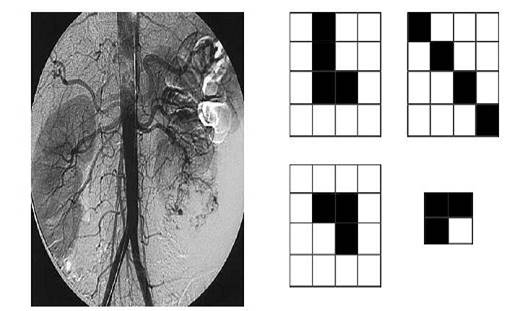

Un uso de los resultados pres&ados en la sección anterior se encu&ra en el filtro de imágenes en escala de grises, lo cual fue explorado por Forero en [10], en este caso se enfocará en imágenes médicas obtenidas por medio de contraste, la imagen que se implem&ará es una arteriografía por substracción digital con el método de Seldinger tomada de la Figura 1. 7 de [12] en formato JPEG, con dimensiones 1441 x 1441 pixeles, para ello se implem&ó el lenguaje Python y el paquete pymorph el cual permite aplicar los operadores erosión y apertura en el caso clásico, admitiendo un elem&o estructural binario.

Con el propósito de &ender la interpretación que realiza el computador de la imagen de estudio es necesario observar la Figura 2, en ella se tiene la implem&ación de los operadores, erosión, apertura y dilatación en el caso clásico, lo cual consiste en trasladar el elem&o estructural a la imagen original, en la Figura 2, el elem&o estructural (observe el círculo rojo en la Figura 2 se sitúa en cada píxel; se toma en el caso de la dilatación la intersección del elem&o estructural con la imagen y en caso de que alguno de los píxeles este pintando, se colorea el píxel, en caso contrario se deja en blanco, una explicación más detallada del caso clásico de la implem&ación de cada uno de los operadores antes mencionados en lenguaje Matlab - Ptyhon puede verse en [7].